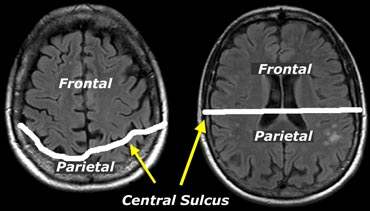

The central sulcus is more posteriorly on more cranial images. The central sulcus is more posteriorly on more cranial images.

When assessing atrophy in different regions keep in mind that cranially, the central sulcus lies more posteriorly than you would expect (figure).